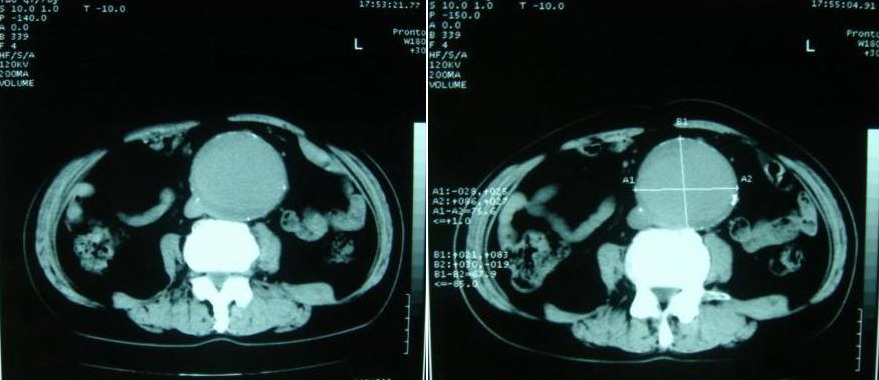

以下是引用why7912在2007-8-29 19:08:00的发言:[br]典型夹层动脉瘤,可见真假双腔及附壁血栓

以下是引用快乐男生在2007-8-29 16:45:00的发言:[br]腹主动脉及右髂总动脉大范围的管径增粗,[br]管壁多发的钙化,[br]并见真假腔(双腔征),假腔可见附壁血栓.[br]考虑腹主动脉夹层动脉瘤 .建议增强或mri